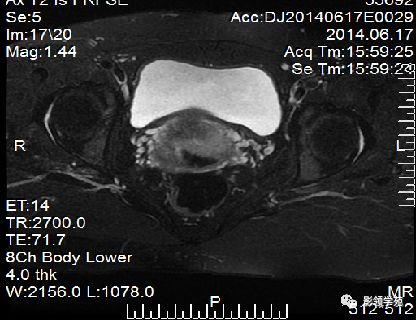

子宫体正常MRI表现

T2WI :

宫颈四层:

高信号---宫颈管黏液

稍高信号---宫颈黏膜皱襞;

低信号---宫颈纤维基质(与宫体JZ连续)

等信号---宫颈肌层

宫颈

T1WI表现为较均匀一致的稍低信号

高分辨率T2WI可看到4层结构

最内层-高信号粘液

粘膜层(柱状上皮)-高信号,低于粘液信号

纤维间质(结合带)-低信号

肌层-中等信号